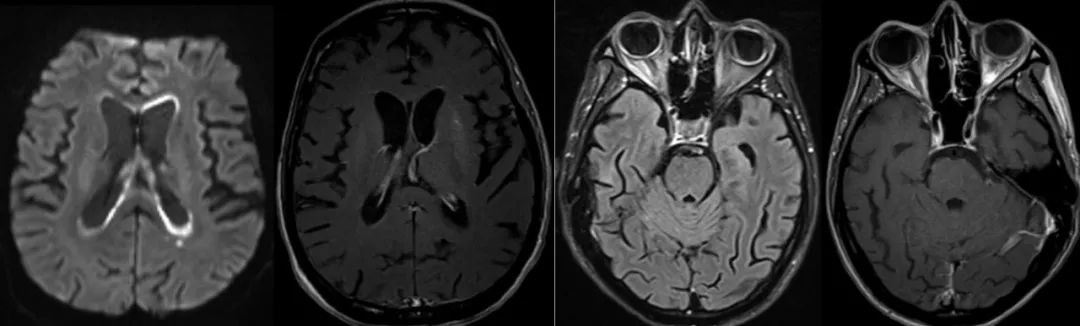

患者21岁,智能减退1年,加重伴行走不稳10天,双手抖动,生活不能自理。同型半胱氨酸(Hcy)>80 μmol/L。患者2017年11月24日头颅磁共振成像如下。

2017年11月28日头CT和12月5日复查头CT如下:

患者确诊为晚发型甲基丙二酸尿症(MMA)伴高同型半胱氨酸血症(cblC型)并发脑出血。本病由于甲基丙二酸单酰辅酶A变位酶(MCM)缺陷或其辅酶钴胺素的缺陷所致,属于常染色体隐性遗传疾病。表现为单纯的MMA或晚发型MMA伴高同型半胱氨酸血症(MMAHC),晚发型MMAHC是我国MMA患者的主要生化表型。MMAHC患者甲基丙二酸和同型半胱氨酸在体内蓄积,导致神经、血液、肝脏、肾脏等多系统损伤。患者MRI表现为广泛的大脑白质疏松,在T2WI相上出现明显的高信号,在疾病的晚期出现白质萎缩和脑室扩大。而单纯的甲基丙二酸尿症患者则以双侧基底节,尤其是苍白球的病变多见,在MRI表现为明显的长T2信号,可伴内囊后肢受累。合并同型半胱酸血症的甲基丙二酸尿症由于甲基基团的减少和异常脂肪酸代谢产物毒性作用,可能是导致患者脱髓鞘病变和白质损害的原因。MMAHC并发脑出血临床少见。